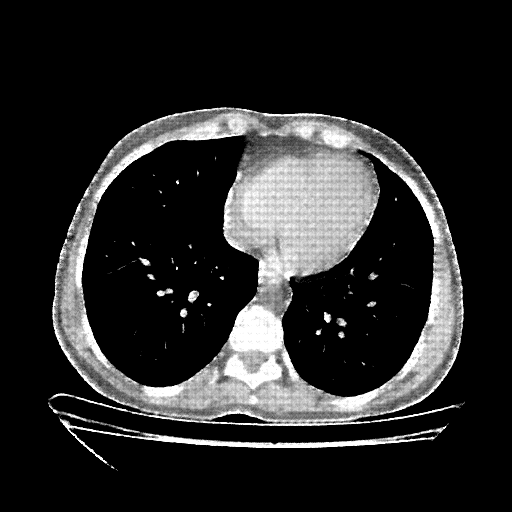

Generated VENOUS CT scan (A→B translation)

No window - Raw intensity values

Lung window (WL -600, WW 1500 β†’ Low βˆ’1350, High +150)

Mediastinum window (WL 40, WW 400 β†’ Low βˆ’160, High +240)